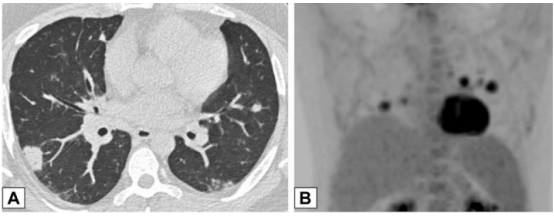

图源:Chest, 2022, 162(1):156-178.图3A为71岁男性,2011年7月因劳力性呼吸困难就诊,胸片显示右肺上叶实变。图3B为2012年6月再次检查显示右肺上叶异常已消失,左肺出现广泛实变。图3C为2013年6月,左肺病变消失,但右肺下叶出现新的实变。这些发现是典型的OP游走性表现。图源:Chest, 2022, 162(1):156-178.图3所示患者胸部CT可见磨玻璃影伴小叶间隔增厚和铺路石征的游走灶(图4)。由此可见,OP的实变可以发生在肺的任何部位,边界清晰或模糊,呈游走性特点。图源:Chest, 2022, 162(1):156-178.OP的实变可以呈局灶性、多发性和弥漫性,也可以表现为结节或肿块。图5所示患者为70岁女性,COVID-19确诊9个月后出现持续气促,CT平扫图像显示支气管血管周围多灶性肿块样实变。在类固醇治疗后症状显著改善,实变消退,推测诊断为OP。图源:Chest, 2022, 162(1):156-178.实变常伴支气管充气征,可伴散在的磨玻璃样低密度或小实质结节。以主要的或完全的磨玻璃低密度为表现者较少见。图6A所示为一名有甲状腺乳头状癌病史的47岁男性患者碘131治疗4个月后的CT平扫图像,可见右肺上叶支气管血管周围磨玻璃影。PET/CT扫描显示磨玻璃影代谢增高(图6B)。CT平扫图像显示左肺上叶新出现的磨玻璃影(图6C)。支气管活检结果与OP相符。图源:Chest, 2022, 162(1):156-178.图7为一名71岁男性患者因使用胺碘酮导致SOP的CT平扫图像,可见左肺广泛磨玻璃影,小叶间隔增厚(铺路石征)。磨玻璃低密度影合并小叶间隔增厚可表现为铺路征。

图源:Chest, 2022, 162(1):156-178.CT扫描图像显示双肺多发小实性结节(图8),提示恶性肿瘤或感染可能。CT扫描引导下针吸活检结果与OP诊断一致。图源:Chest, 2022, 162(1):156-178.42岁患者,病态肥胖,有呼吸困难,右肺上叶(图9A)和右肺下叶(图9B)CT平扫图像显示双侧、胸膜下或周围肿块样实变区域。这些发现为非特异性;活检结果提示OP,类固醇治疗后消退。图源:Chest, 2022, 162(1):156-178.OP以结节为主的影像学表现,范围从小的微结节(直径<4 mm)到较大的离散结节(直径通常达1 cm),以及较大的结节或肿块。较大的结节或肿块常被描述为具有不规则或锐利边缘,通常包含支气管充气征。图10所示为一名接受美沙拉嗪治疗的38岁男性溃疡性结肠炎患者出现气促。A为后外侧胸片,显示双肺多发结节。胸部CT增强扫描显示结节为周围型和支气管血管周围型,一些伴有气道扩张(B和C中的箭头)。粗针穿刺活检结果与OP相符。图源:Chest, 2022, 162(1):156-178.此外,结节可以单发或多发,通常为实性结节或部分实性结节。图11为一名73岁男性吸烟者低剂量CT,CT平扫图像显示右肺上叶孤立的不规则结节影,伴有细微的气道扩张(A中箭头)。支气管内超声引导下细针活检结果符合局灶性OP表现。图源:Chest, 2022, 162(1):156-178.临床中遇到影像学表现为结节的情况,需要注意与肿瘤相鉴别。PET扫描对这些病变的评估显示标准化摄取值轻微升高,但结果为非特异性,临床价值有限。图12所示为PET扫描一名无症状、有乳腺癌病史并长期使用呋喃妥因的70岁女性,CT平扫图像显示双肺下叶不规则、实性结节。由于担心转移性疾病,进行了PET扫描(图12C),轴位PET图像显示左肺下叶结节(B、C中箭头)是FDG高摄取。左肺下叶结节的粗针穿刺活检结果与OP相符。图源:Chest, 2022, 162(1):156-178.34岁女性患者因系统性红斑狼疮就诊,表现为气促。胸部CT显示双肺多发大小不等的实性结节,包括左肺基底部微小结节改变(图13A)。FDG-PET扫描的图像显示结节为高代谢(图13B)。两个结节的楔形活检结果符合OP诊断。图源:Chest, 2022, 162(1):156-178.以线状或网状为主的OP影像特点包括表现为线状不透明的实质条带,通常延伸到胸膜表面,先于磨玻璃影或实变。图14所示为条带活检证实为OP的同一患者间隔1年进行的CT扫描,可见患者双肺下叶条带部分消退(A、B中箭头)。